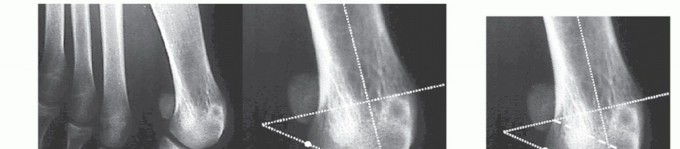

The HVA is determined by the intersection of the diaphyseal axes of the first metatarsal and the proximal phalanx. Arbitrarily, a normal HVA does not exceed 15 degrees (FIG 1A).

The IMA is the angle between the diaphyseal axes of the first and second metatarsals. Arbitrarily, a normal IMA does not exceed 9 degrees (FIG 1B).

Sesamoid position grades 1 to 3: Grades 1 through 3 signify an increasingly greater lateral position of the tibial sesamoid relative to the bisecting line of the tibial shaft axis, with grade 3 indicating that the tibial sesamoid is positioned completely lateral to the reference line (FIGS 1C and 2).

FIG 1 • AP radiograph of a patient with hallux valgus. Left, HVA (up to 15 degrees). Second from left, first IMA (up to 9 degrees). Second from right, sesamoid position. In this patient, the tibial sesamoid is divided into two halves by the diaphyseal axis of the first metatarsal, which means the beginning of a grade 2

sesamoid subluxation (normal is grade 0). Right, relative length of the first and second metatarsals; normal is up to 5 mm.

FIG 2 • Evaluation of hallucal sesamoid position. Grade 0, no displacement of sesamoids relative to the middle diaphyseal axis of the first metatarsal (normal). Grade 1, overlap of less than 50% of the tibial (medial) sesamoid to the reference line. Grade 2, overlap of more than 50% of the tibial sesamoid to the reference line. Grade 3, tibial sesamoid completely displaced beyond the reference line.